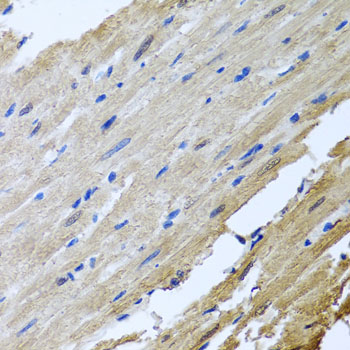

Immunohistochemistry of paraffin-embedded rat heart using CAMK2G at dilution of 1:100 (40x lens).